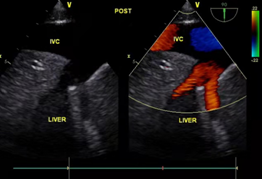

祁彦(化名)有子宫肌瘤病史,14年前在当地医院做过切除手术。一月前体检提示心脏肿瘤,B超提示:中下腹及盆腔内见巨大占位,与子宫关系密切,右侧髂内静脉经髂总静脉、下腔静脉延伸至右心房内可见中等低度回声,测右房内大小为34*51mm,心房内瘤体较大。

手术前后B超对比

12月4日,手术当日,妇产科陈必良教授、马佳佳医生开腹,游离出巨大的子宫肌瘤及双侧附件,切除后分离出瘤体远端,游离下腔静脉。心血管外科董小超副教授开胸在心脏不停跳并行体外循环下切开右房,探查右房内瘤体情况,通过腹部切口,将髂静脉切开分离肿瘤,于肿瘤起始部位切断肿瘤,自右心房内取出瘤体。循环稳定,术中食道超声持续观察以确定心内瘤体彻底取出。患者病变子宫极大,瘤体呈圆柱形,长约30-40cm。术后患者转入心血管外科监护室继续监护治疗。术后当天,患者恢复自主呼吸,生命体征平稳,顺利拔管。病情稳定后安返病房,与家人团聚。